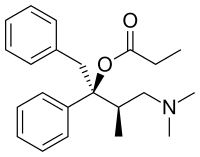

The pharmacodynamic response to an opioid depends upon the receptor to which it binds, its affinity for that receptor, and whether the opioid is an agonist or an antagonist. For example, the supraspinal analgesic properties of the opioid agonist morphine are mediated by activation of the μ1 receptor; respiratory depression and physical dependence by the μ2 receptor; and sedation and spinal analgesia by the κ receptor. Each group of opioid receptors elicits a distinct set of neurological responses, with the receptor subtypes (such as μ1 and μ2 for example) providing even more [measurably] specific responses. Unique to each opioid is its distinct binding affinity to the various classes of opioid receptors (e.g. the μ, κ, and δ opioid receptors are activated at different magnitudes according to the specific receptor binding affinities of the opioid). For example, the opiate alkaloid morphine exhibits high-affinity binding to the μ-opioid receptor, while ketazocine exhibits high affinity to ĸ receptors. It is this combinatorial mechanism that allows for such a wide class of opioids and molecular designs to exist, each with its own unique effect profile. Their individual molecular structure is also responsible for their different duration of action, whereby metabolic breakdown (such as N-dealkylation) is responsible for opioid metabolism.

- Esters of morphine opiates: slightly chemically altered but more natural than the semi-synthetics, as most are morphine prodrugs, diacetylmorphine (morphine diacetate; heroin), nicomorphine (morphine dinicotinate), dipropanoylmorphine (morphine dipropionate), desomorphine, acetylpropionylmorphine, dibenzoylmorphine, diacetyldihydromorphine;[261][262]

Tramadol and tapentadol, which act as monoamine uptake inhibitors also act as mild and potent agonists (respectively) of the μ-opioid receptor.[264] Both drugs produce analgesia even when naloxone, an opioid antagonist, is administered.[265]